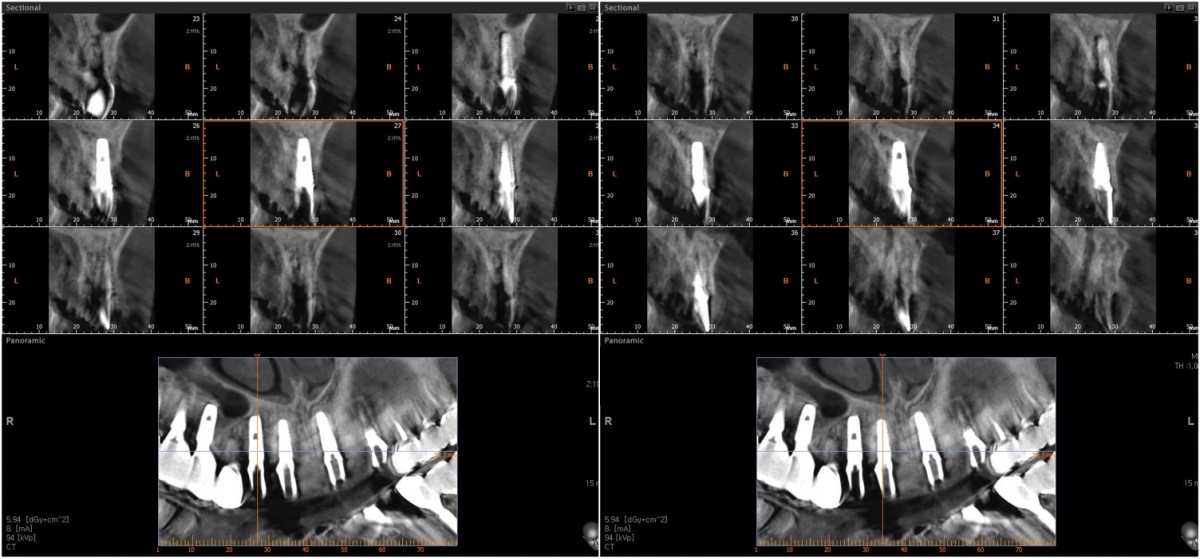

Anterior implant placement with Arum implant system in the maxilla.

A 46-year-old female patient didn’t

have any systemic problems but a poor oral condition.

The patient is scheduled

for the implant and general prosthetic restoration in various parts. First of

all, the vertical stop is completed by several prostheses in the posterior

region, and the final stage of intraoral restoration is to proceed with an

anterior implant installation.

▲Fixture to be placed. Arum® implant NB1